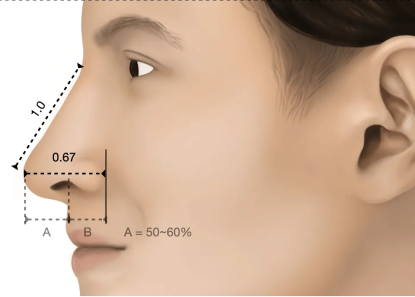

Similar to the golden ratios of beauty, the nasal tip should form a harmonious triangle with the precise tip-defining points to create the ideal nose.

Ideal Triangle and Tip-Defining Points

Similar to the golden ratios of beauty, the nasal tip should form a harmonious triangle with the precise tip-defining points to create the ideal nose.